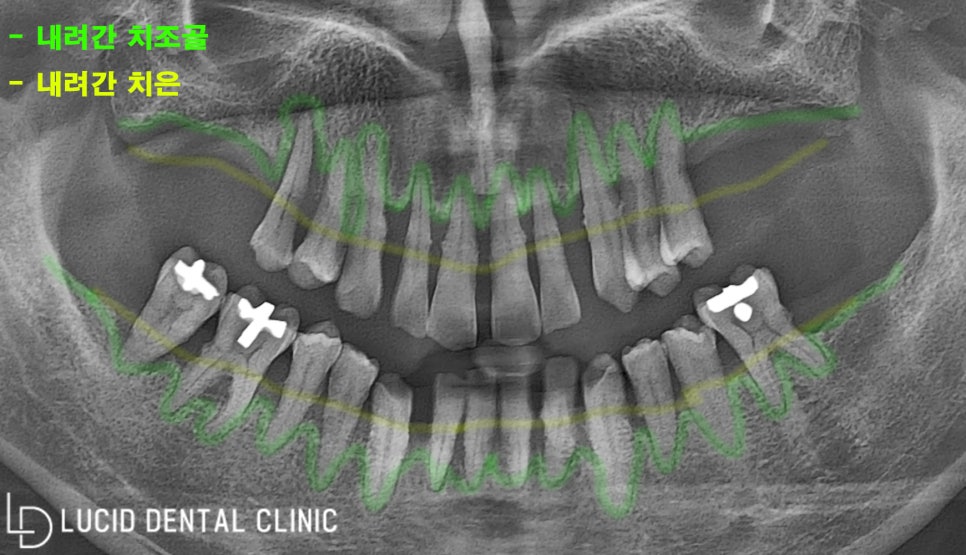

이제 파노라마 사진을 한 번 봐 볼까요?

우선 전체적으로

치은과 치조골이 내려가 있고,

곳곳에 염증이 발생했습니다.

그리고 부정교합을 가지고 계셨는데

치석과 치태가 오래 쌓여

두껍게 축적되어 있었는데요.

아무래도 구강 관리를

소홀히 하셨던 것 같습니다.

심지어 전체적으로

동요가 매우 높았는데요.

치료가 굉장히

시급해 보였습니다.